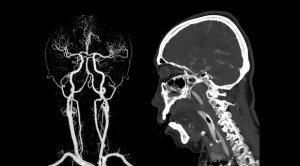

• CT Angiografi Diperluas vs CT Angiografi Standar dalam Penatalaksanaan Stroke Iskemik – Telaah Jurnal Alomedika

CT Angiografi Diperluas vs CT Angiografi Standar dalam Penatalaksanaan Stroke Iskemik – Telaah Jurnal Alomedika

Extended CT angiography versus standard CT angiography for the detection of cardioaortic thrombus in patients with ischaemic stroke and transient ischaemic attack...(Baca Selengkapnya)